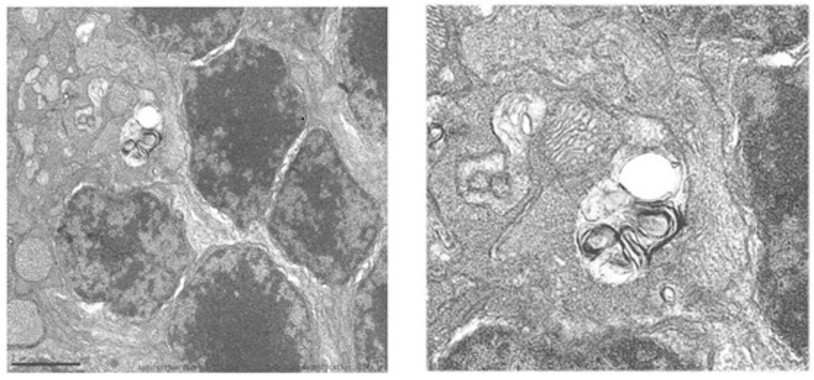

Un estudio revela cómo las células tumorales secuestran células sanas para promover la metástasis

21/02/2017